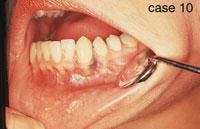

CASE 10

Amalgam tattoo

1. What is the appearance of the amalgam tattoo?

a. blue, black or gray color

b. diffuse border

c. flat

d. any of the above

2. How is the amalgam tattoo most often diagnosed?

a. clinical features

b. histologic features

c. radiographic appearance

d. both a & c

3. What is the recommended treatment for the amalgam tattoo?

a. no treatment necessary

b. surgical removal

c. radiation therapy